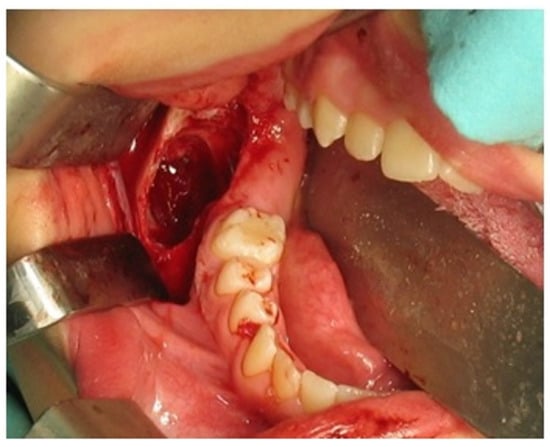

2. Case Report Presentation